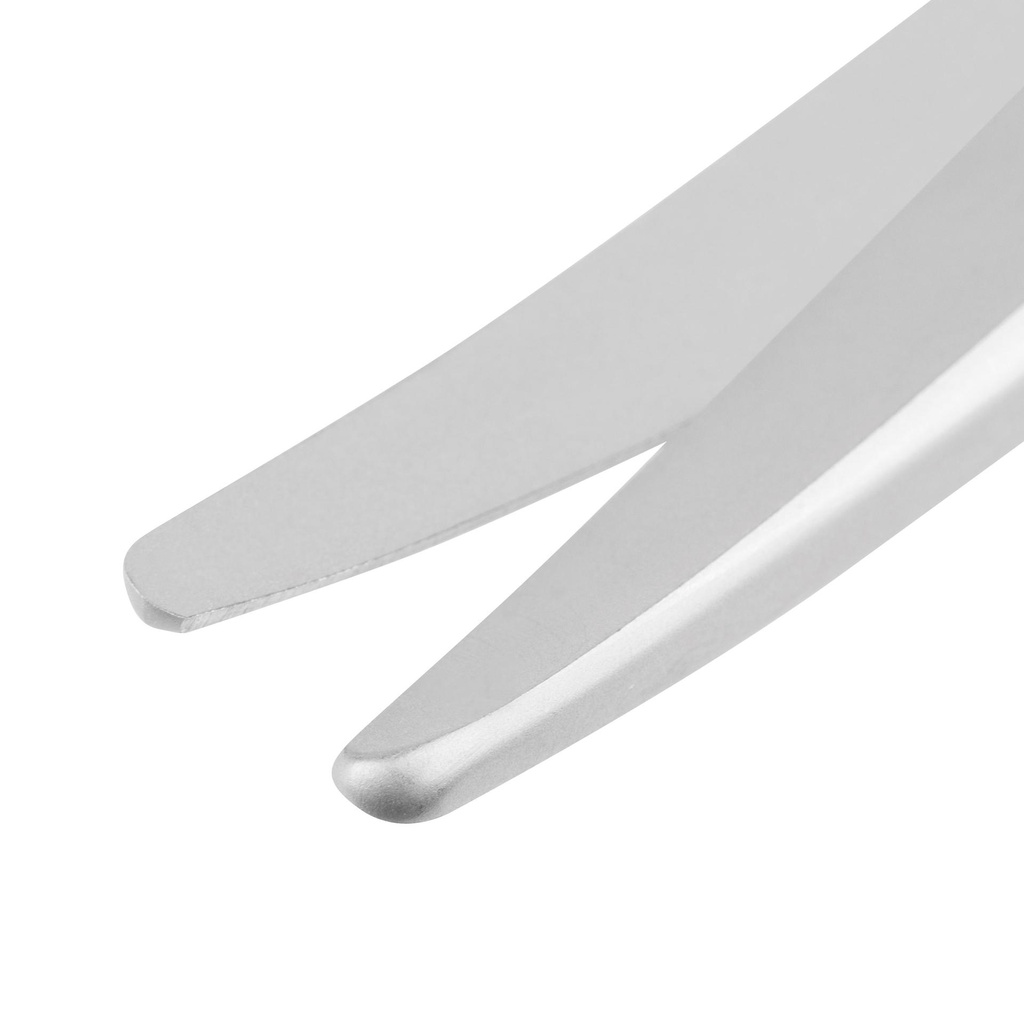

Schaar Mayo gebogen 14 cm

- Stomp/stomp

- Vorm: gebogen